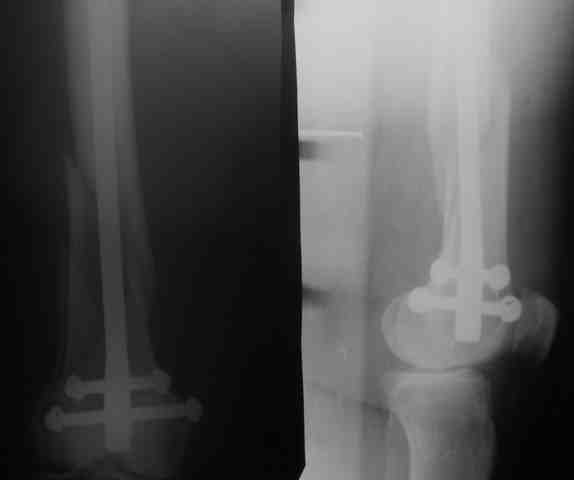

Попутно, разрешите поделится опытом закрытого ретроградного синтеза бедра. Внедрение тяжелая штука, пости года 2 прошло со времени обучения методике. Использовать/убедить использовать дистрактор на бедре/голени удавалось редко. Отлично дистрактор прижился на плече. Зав. отделением не знал точного плана операции(поэтому не смог помешать).Стокнулись со следующей проблемой - при попытке устранить ротацию теряли длину, при дистракиции получали ротацию, при чем при ротации телескопы очень плотно давят на бедро. Больная с ожирением, на ощупь проводили спицу проксимальной опоры, пульсацию бедренной артерии для ориентира определить не возможно. Проксимально латеральный телескоп все время оказывался длиннее, чем надо, меняли его положение.Не смотря на все это, считаю, без дистрактора данная операция заркрыто не возможна , особенно в наших условиях.

Успешный опыт пользвания дистрактором есть(я сам видел, не видел бы- бросил бы попытки пользования дистрактором). Пожалуйста, укажите на допущенные ошибки. Спасибо.

Рг в приложении.